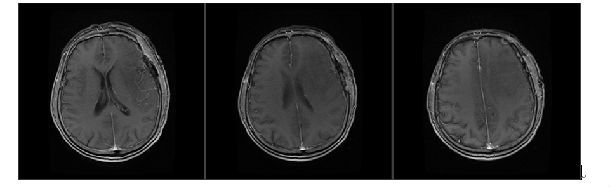

术后3天复查MRI,无肿瘤残余。